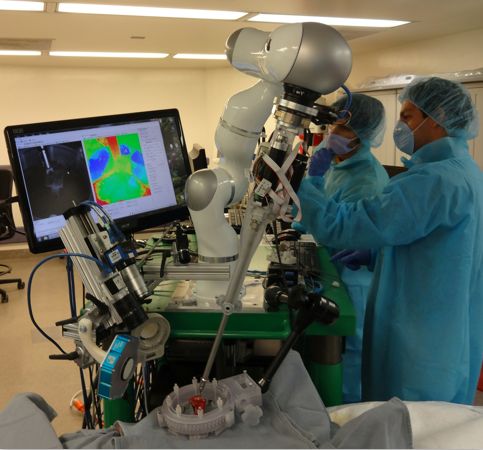

机器人辅助手术

在价值潜力方面,机器人辅助手术是人工智能辅助方向的佼佼者。AI-enabled机器人技术可以通过集成实时操作矩阵、来自实际手术医生的数据以及来自手术前病历的信息来提高和指导手术器械的精度。事实上,埃森哲报告说,人工智能机器人技术带来的进步缩短了21 %的停留时间。

研究各种解决方案,我发现Mazor机器人最有希望。它使用AI来最大限度地减少侵入性(invasiveness),并最大限度地制定解决具有复杂解剖结构的区域(如脊柱)的外科手术。AI系统帮助外科医生在病人出现之前,通过CT扫描将植入物(implant)放在指定的位置,Mazor的脊柱外科机器人臂引导外科器械的运动,确保高度的精度。